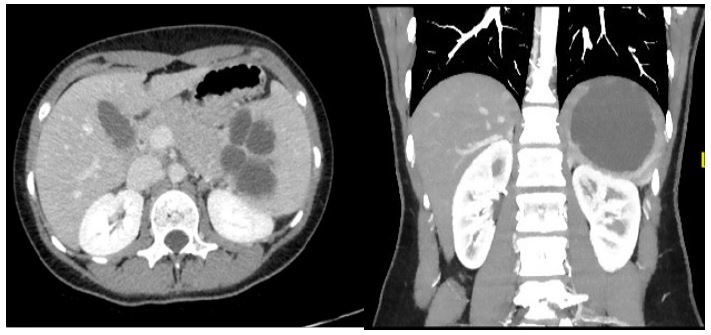

We report the case of a 14-year-old girl who complained of aspecific recurrent abdominal pain. An abdominal ultrasound was performed, showing an anechoic cystic lesion of 14 mm of diameter in the superior pole of the spleen, without evidence of splenomegaly. We started an annual follow-up and after three years the ultrasound showed an increase in size of the splenic cyst, reaching 97 mm of diameter. The subsequent diagnostic work-up included blood exams that were found normal and a negative serology for Echinococcus granulosus. We also performed an abdominal Magnetic Resonance (MR) and Computed Tomography (CT) that showed a cystic lesion at the upper pole of the spleen, characterized by a single thin wall with a low density fluid content and multiple septa. The size of the cyst was 11x9x9 cm with no evidence of calcifications or further splenic lesions. The bipolar diameter of the spleen was 14.5 cm, with a compression of the stomach and dislocation of the left kidney (Figures 1,2). Based on to the radiological findings and on the progressive growth of the lesion we suspected a diagnosis of isolated splenic cystic lymphangioma.

Figure 2: Preoperative abdominal CT scan: Compression of the stomach and dislocation of the left kidney due to splenomegaly and a cystic lesion with single thin wall, low density fluid content and multiple septa. No calcifications are present.